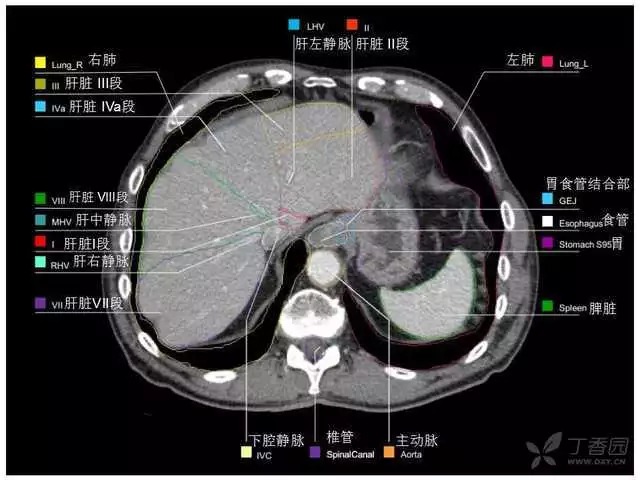

腹部肝脏高清CT断层的图谱

全腹部高清CT图谱,淋巴结彩色图谱,血管解剖图谱大汇总!

肝段,肝内管道的分布规律

美国放射学会ACR官网,对肝脏的区域和节段解剖学概述